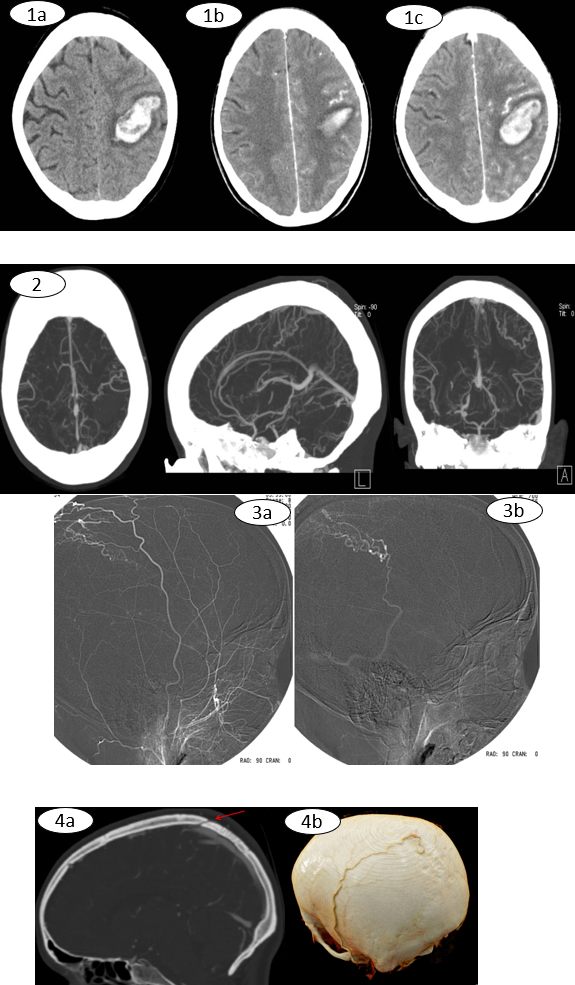

Figura 1. Cortes axiales de TC secuencial de cráneo sin (a) y con (b,c) contraste iv.

Hematoma intraparenquimatoso lobar parietal izquierdo de 48 mm de diámetro mayor con leve edema perilesional (1a). Tras administración de contraste se visualiza prominencia de una estructura vascular anómala cercana al hematoma (1b,1c).

Figura 2. Reconstrucciones multiplanares de AngioTC de troncos supraaórticos Estructura vascular anómala prominente en vecindad a la localización del hematoma.

Figura 3.  Arteriografía selectiva de carótida externa izquierda Imágenes sagitales adquiridas en fase precoz (a) y más  tardía (b). Fístula dural en región parasagital parietal posterior izquierda con aferencias desde ramas parietales posteriores de la arteria temporal superficial izquierda (3a) y drenaje venoso retrógrado a venas corticales dilatadas que mediante colaterales termina drenando al seno transverso izquierdo (3b).

Figura 4.  Reconstrucciones multiplanares (a-sagital y b VRD) del cráneo. Orificio de entrada craneal (4a) de la aferencia vascular proveniente de la arteria temporal superficial izquierda, cuyo recorrido por la superficie craneal se observa en la reconstrucción 3D (4b) .